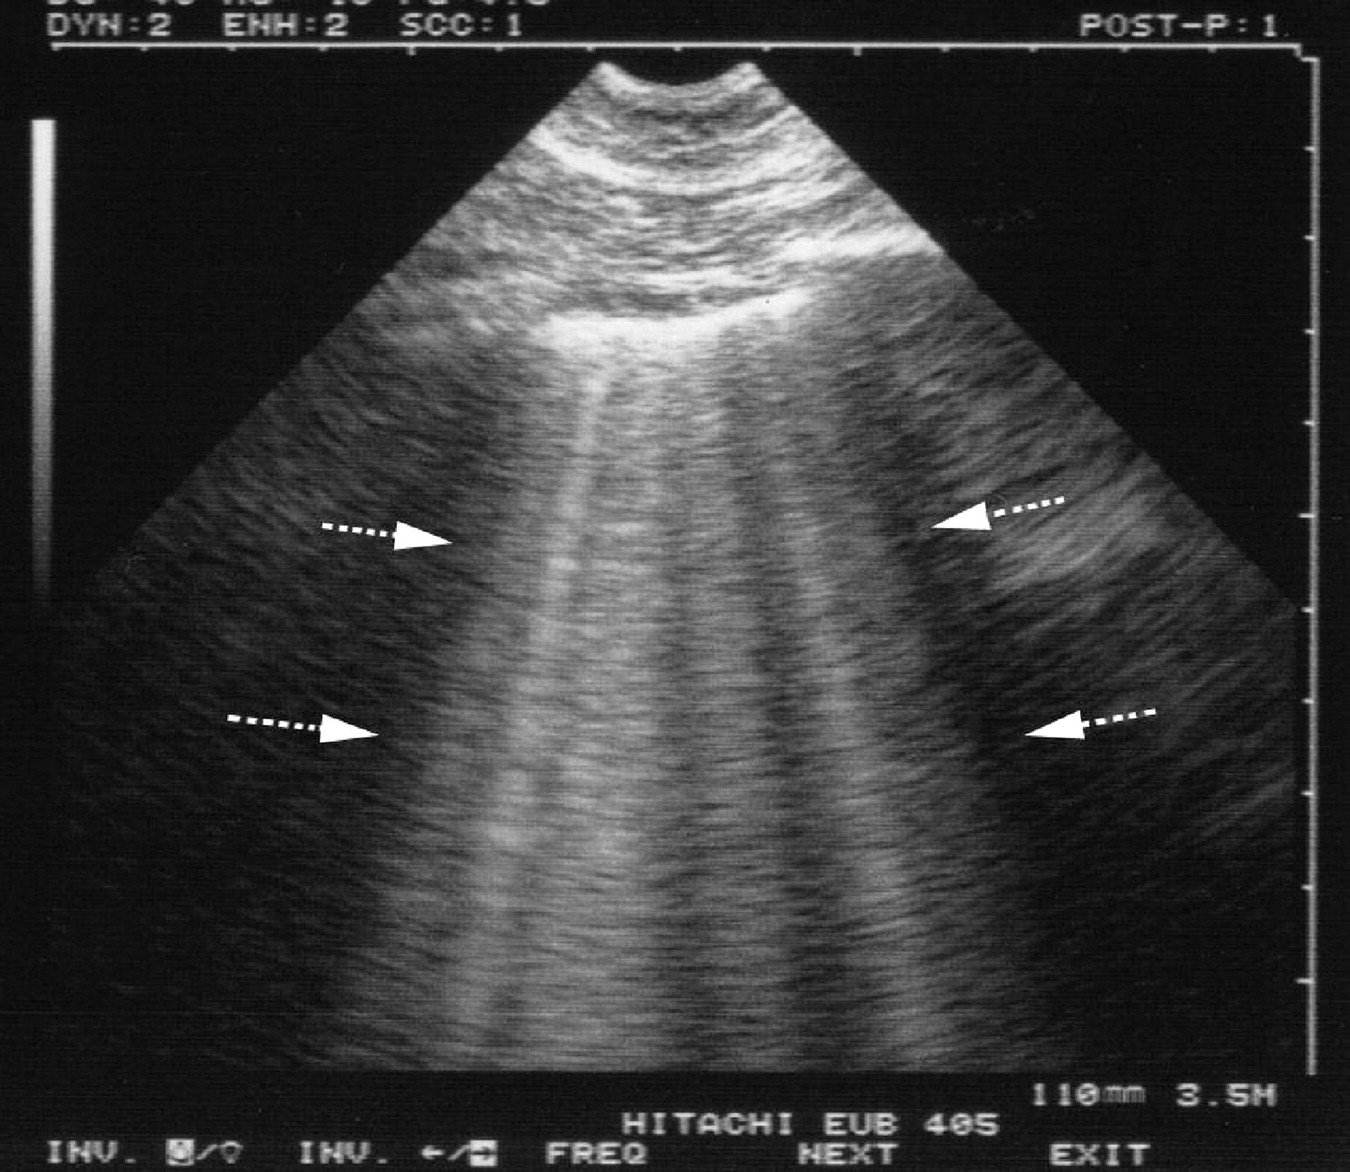

Selected chest ultrasound images. a) Seashore sign. Granular